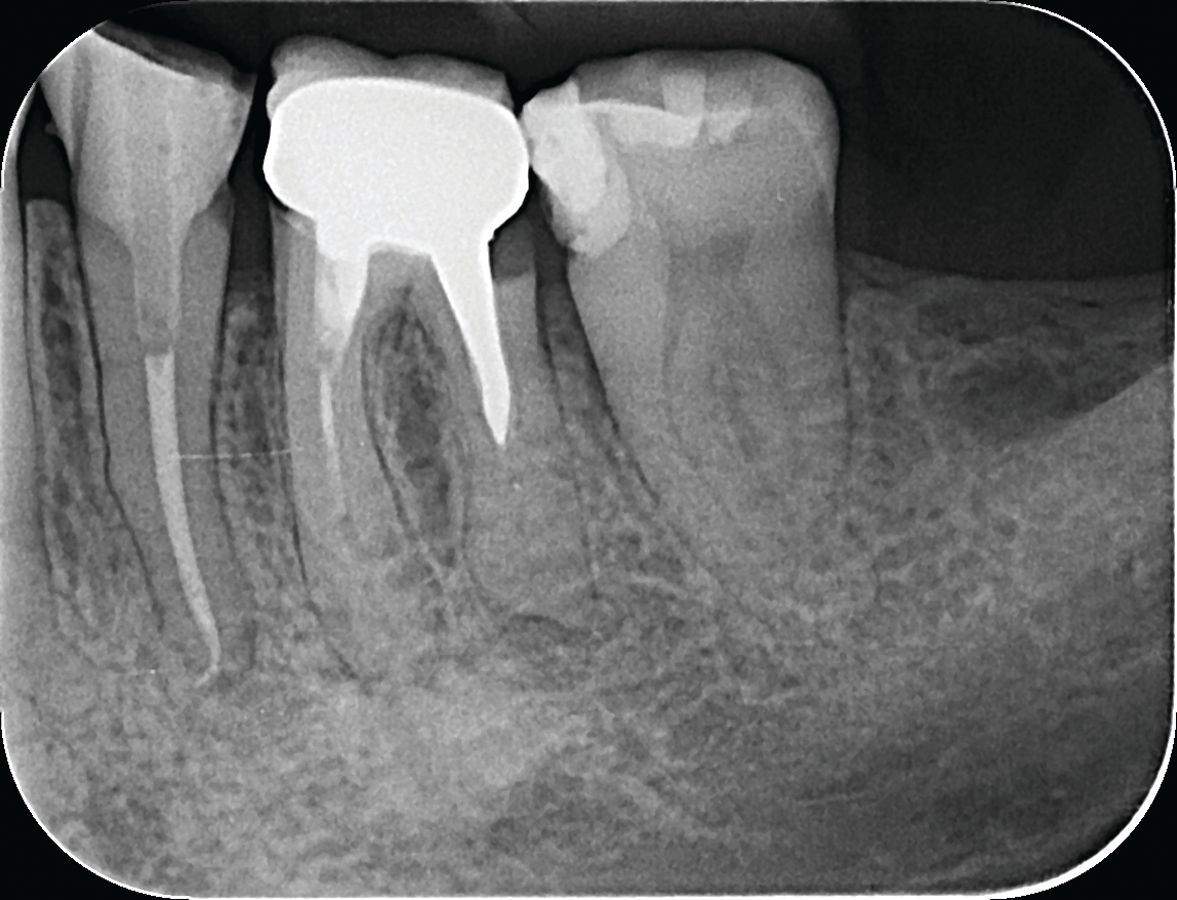

A 46-year-old woman presented to our dental clinic complaining of pain during chewing and a persistent “bad smell” emanating from tooth #19. Radiographic examination revealed a periapical lesion and subgingival distal decay (Figure 1). Additionally, the tooth was tender upon percussion, indicating an acute issue that needed immediate attention.

Figure 1. Radiograph of tooth #19 with pre-existing crown, visible periapical lesion, calcified canal and subgingival distal decay.